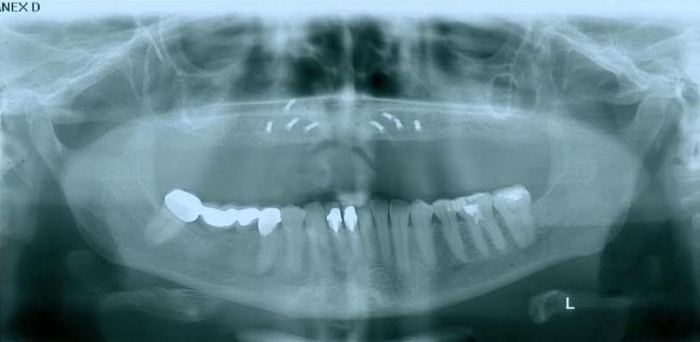

Raio-x Inicial

Raio - x Panorâmico Enxerto ósseo de crista iliáca